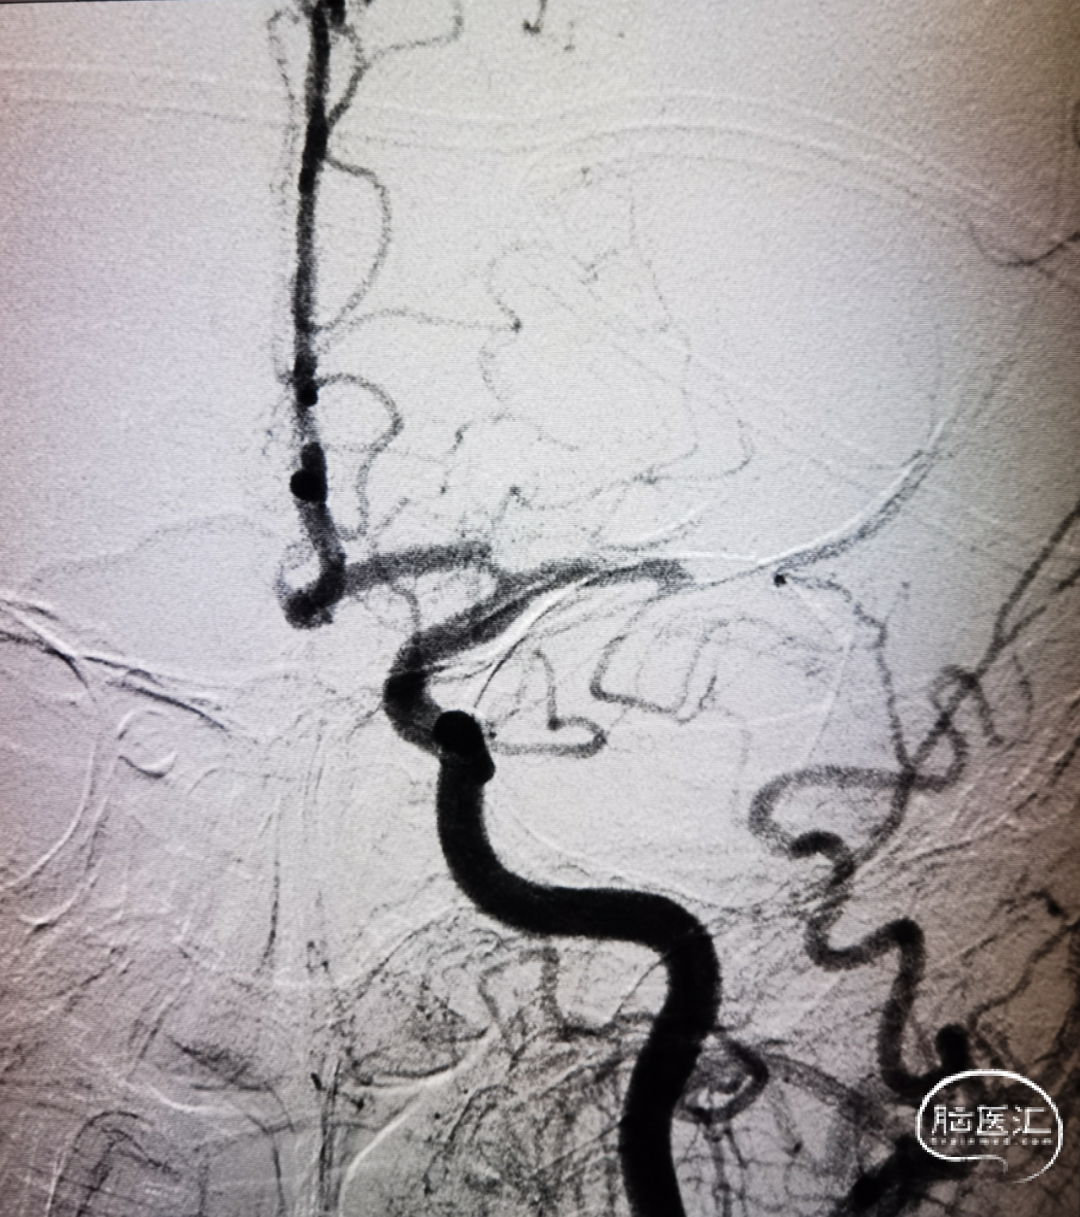

沿取栓支架的输送导丝送入SacSpeed®球囊扩张导管,将球囊置于狭窄段充盈球囊进行扩张。

完成扩张后。

球囊泄压后利用Syphonet®取栓支架的锚定效果让中间导管靠近闭塞段;撤出快交球囊后采用SWIM技术取栓;术后造影证实血管再通。

开通后血流再次闭塞,考虑球扩后夹层形成可能;补救性予以电解脱释放Solitarie支架后正侧位造影。

术中造影确认脑血流完全恢复,mTICI 3级,术后24小时复查头颅CT左顶叶少量渗出。